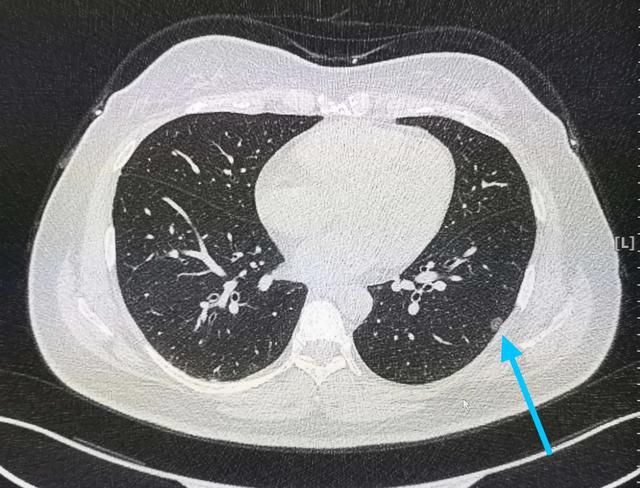

经典早期肺腺癌之肺原位腺癌ct表现